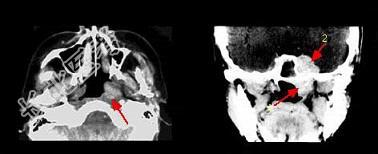

单项选择题哪项不符合腺样囊性癌的肿瘤(如组图)生物学行为 ( )

A、常出现神经症状

B、血行转移率高

C、区域淋巴结转移率高

D、肿瘤易沿神经生长

E、侵袭性极强